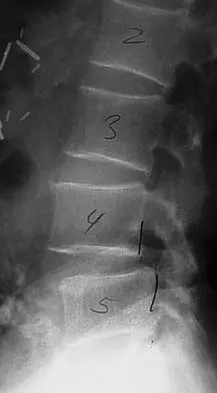

Figures 9a and 9b show the spinal radiographs of a 3-year-old child with short limb dwarfism. The lateral radiograph is obtained with maximal lumbar extension. Management should consist of

Explanation

The patient has kyphosis in association with achondroplasia. The AP radiograph shows decreased interpedicular distance at the lower lumbar vertebrae, a feature considered to be a distinctive sign of achondroplasia. Most patients with achondroplasia have kyphosis, and this usually resolves spontaneously. When the fixed component is greater than 30 degrees, however, brace treatment is recommended. Spinal fusion is seldom required.